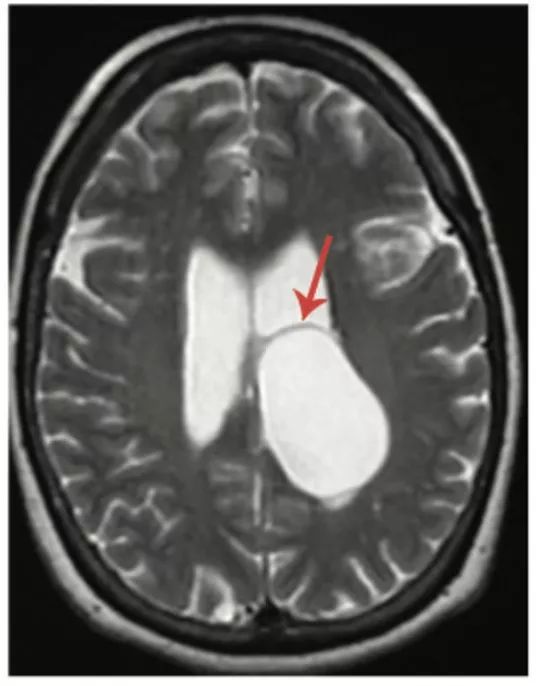

图9 室管膜囊肿

轴位T2WI像显示一个大的脑室内囊肿,等CSF信号,引起右侧侧脑室扩张,可见囊壁(箭头)。